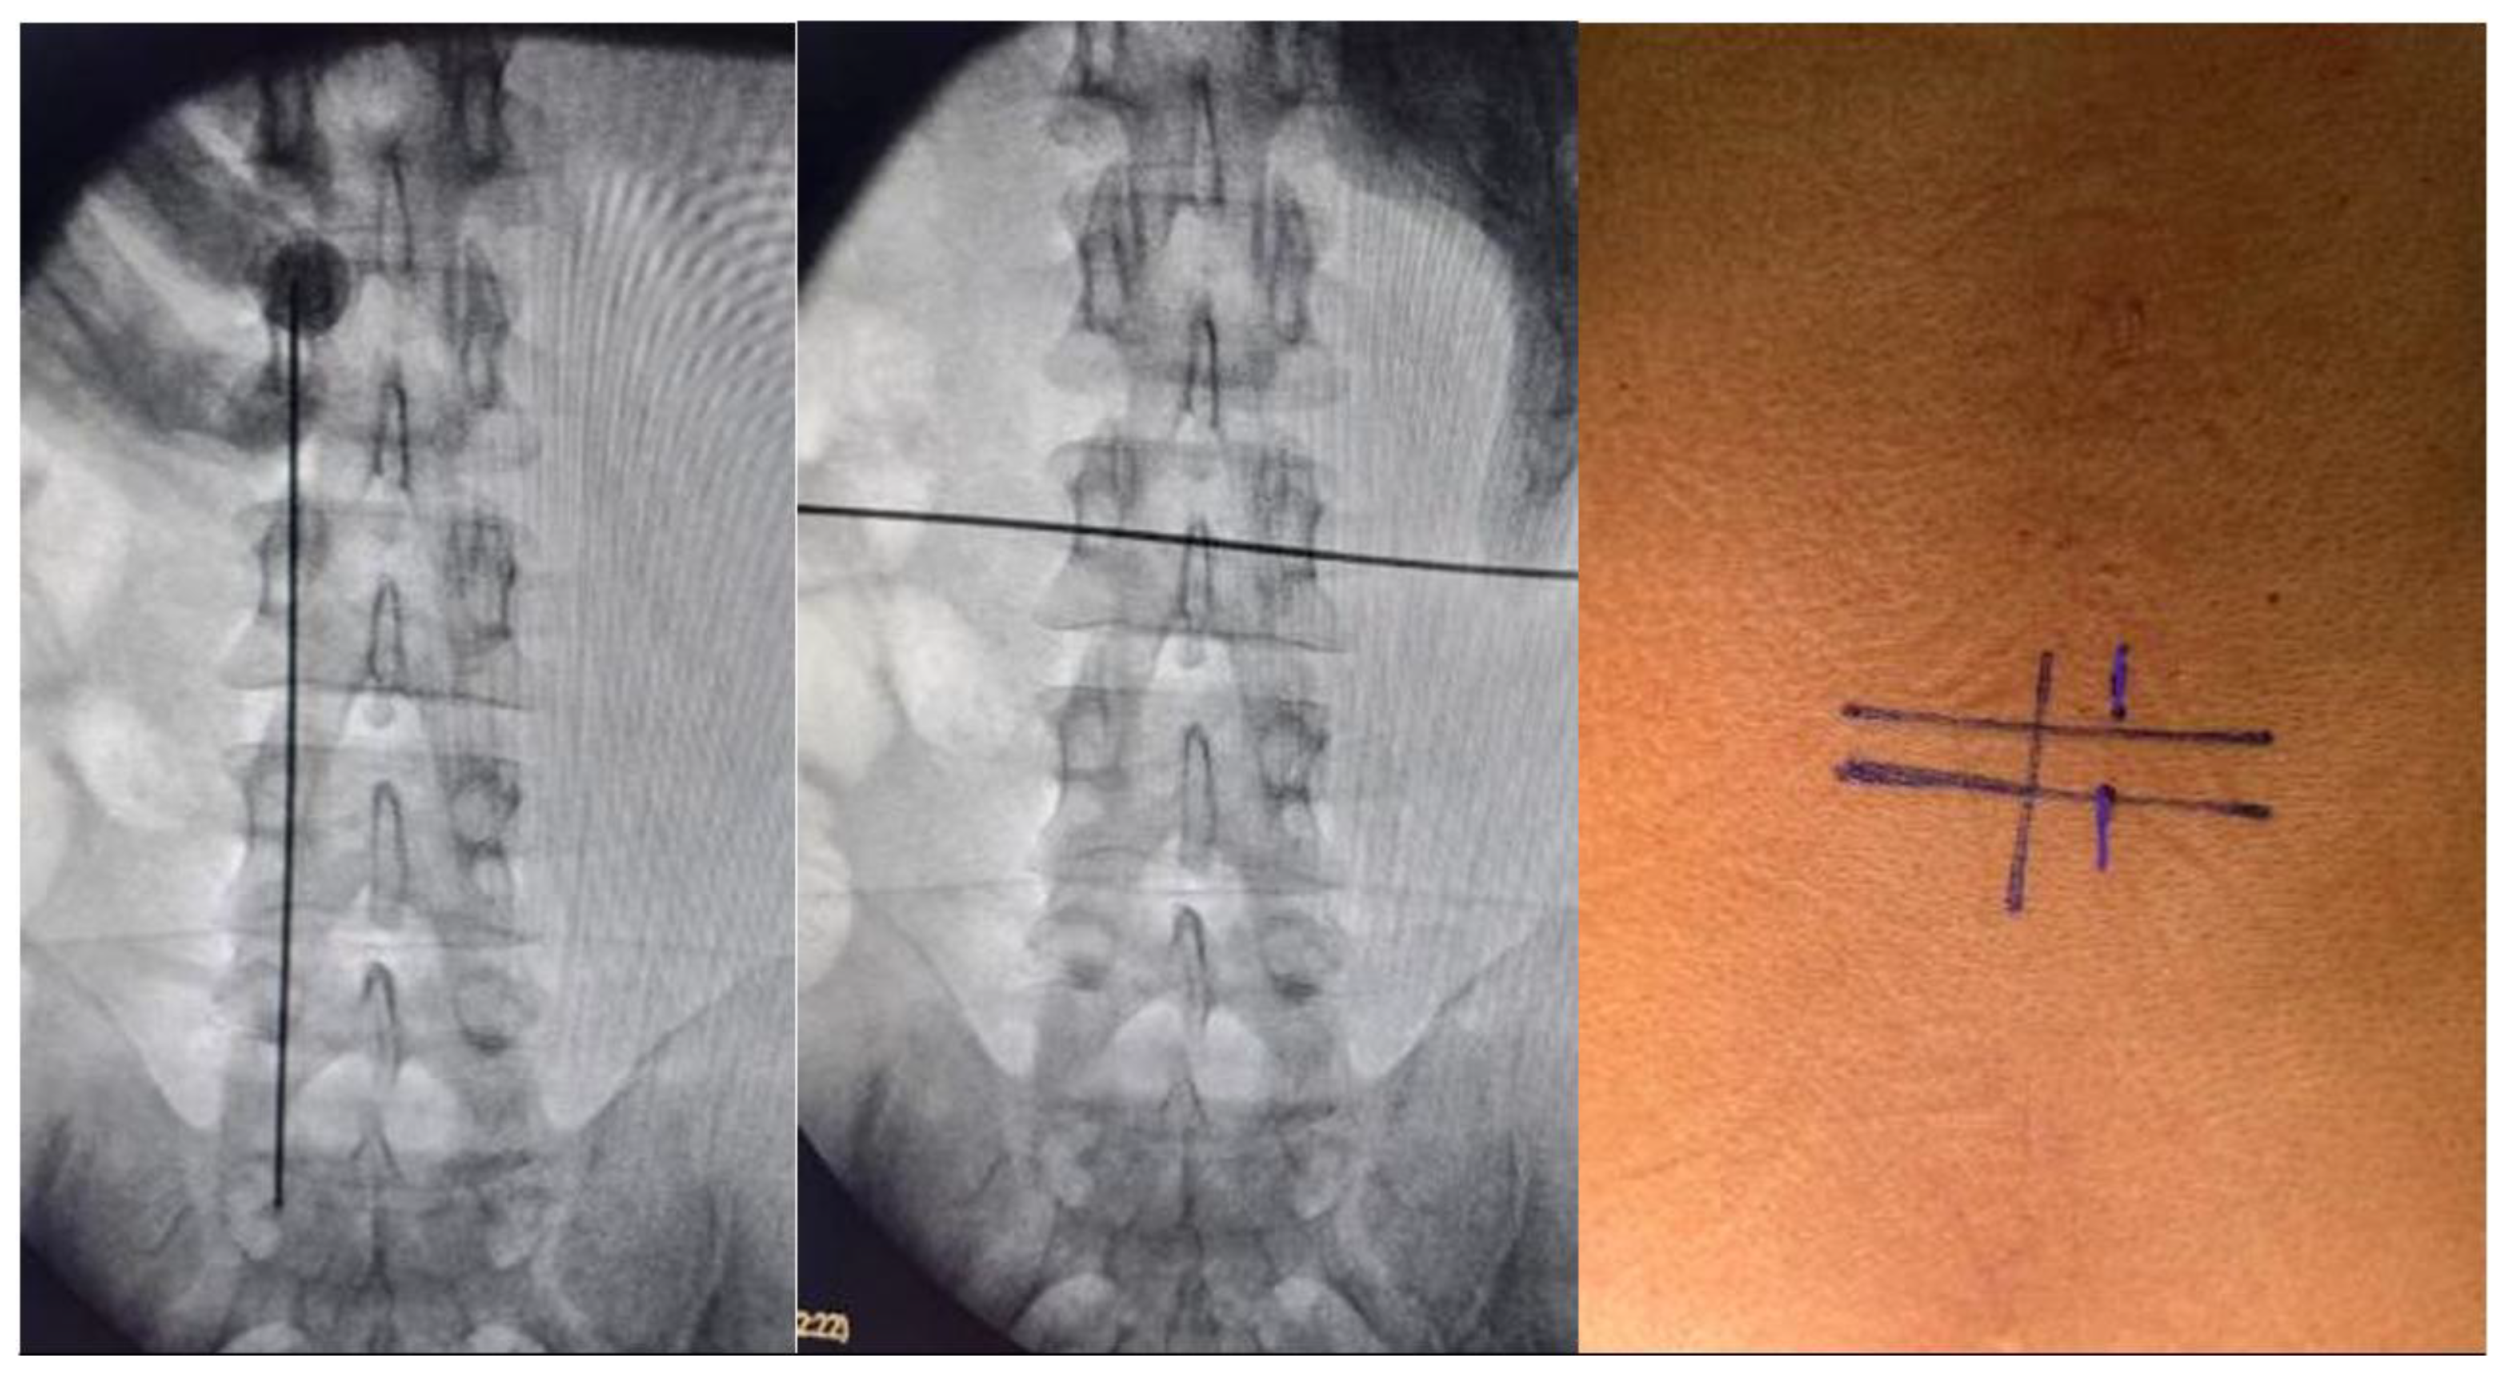

Surgical planning was to perform this procedure with two small incisions with the UBE technique, using a right-sided approach in 8 tumors and 3 with a left-sided approach with fluoroscopy main spinometric marks on the mid-pedicular lines for the right-sided approach and infra-pedicular lines in horizontal plain for the left sided approach and medial pedicular line in vertical plain, we recommend take ap and lateral image to confirm the location, this to achieve a better movement on the tissues and flexibility at the time of durotomy and tumor dissection, we recommend perform a midline durotomy, but this can be modifiable depending on the location of the lesion. The patient was positioned on a classic prone on a radiolucent operating table. We arm the operating room in a classical way for biportal endocopy surgery. (Figure 1, Figure 2 and Figure 3).

We present the case of a 58-year-old female with 2 months of progressive left leg radiculopathy with a leg VAS 9/10, low back pain, back VAS 7/10, and weakness in both lower limbs, with gait impossibility, and neurogenic bladder, MRI revealed a L2-L3 intradural extramedullary lesion that occupies 80% of the spinal canal (Figure 1), as previously described we plan are surgery with UBE technique, with a right side approach, with the spinometric landmarks (Figure 2), with minimal muscular tissue disruption, with bilateral laminotomy of the cephalic and caudal lamina with wider O-cut with over the top technique and flavectomy with Kerrison’s rongeur and curettes, we do a mid-line durotomy with a single cut with 11 blade scalpel and wide de incision with Rhoton dissector, visualize the tumor and perform the dissection with Rhotons and Penfield’s, water dissection increasing the pump flow and then extract the lesion with pituitary forceps without complications over the procedure. We perform closure with a 6-0 prolene suture with the previously described technique. (Figure 3)

Figure 2. Spinometric landmarks to right sided approach.